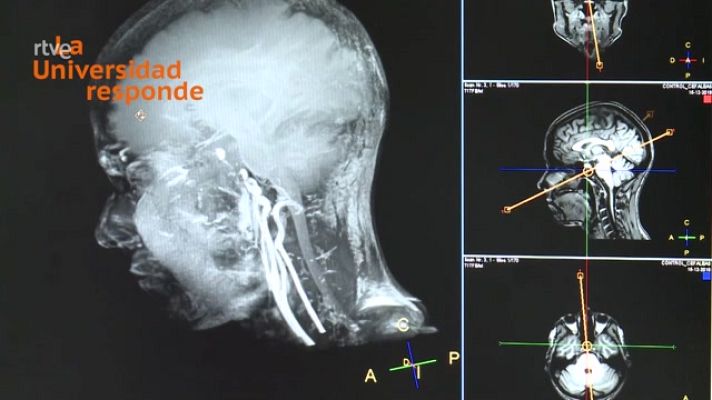

¿Es peligroso hacerse una resonancia magnética?

¿Es peligroso hacerse una resonancia magnética? Universidad de Valladolid. La Universidad Responde.